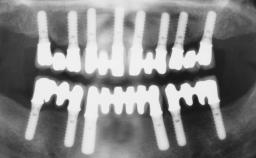

Immediate Loading of Six Implants in the Mandible and Six Implants in the Maxilla and Final Restoration with Full-Arch CAD/CAM Metal Framework FDPs Involving Digital Planning and Guided Surgery

Immediate loading of dental implants is increasingly popular with clinicians and patients. The idea of delivering a restoration directly after implant insertion,combined with a less invasive procedure (flapless protocol), has made treatment protocols involving dental implants more accessible to dentists and patients. However,immediate-loading concepts require sophisticated and exact planning. To facilitate this, conventional panoramic tomographs and periapical radiographs are often taken with the patient wearing a radiographic template simulating the preoperative prosthetic design. However, these radiographs do not provide all the necessary information. In addition, some protocols call for conventional surgical templates fabricated on the diagnostic cast. These will inform the bone drilling points and drill angles, but do not reference the underlying anatomical structures or provide exact 3-D guidance.

# of Implants 12

Guided Surgery Yes